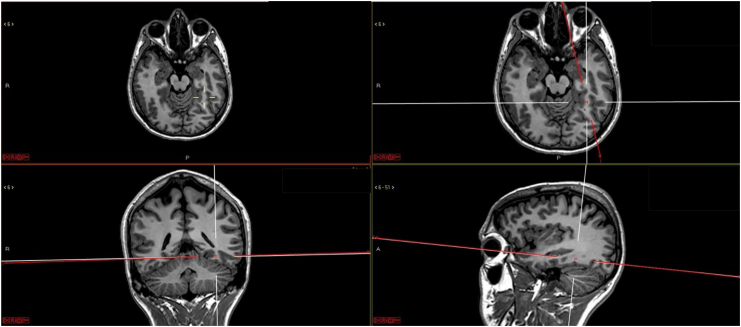

本综述的第二部分试图解释为什么只有智人发展了语言。需要指出的是,这篇综述基于一位临床神经学家的观点,并不打算超越对这一复杂话题的概述。语言的逐步发展可能是由于前额叶皮层(PFC)及其网络的扩展。前额叶皮层是人类大脑皮层中最大的区域,其扩展程度远远超过其他灵长类动物。要实现语言,还需要实现其他一些功能,包括抽象、推理、扩展工作记忆和执行功能。所有这些功能都与前脑皮层密切相关,而语言对它们都有深远的追溯影响。语言和文化会对大脑产生解剖学和生理学上的改变。学习阅读就是文化如何改变大脑的一个例子。

The second part of this review is an attempt to explain why only Homo sapiens developed language. It should be remarked that this review is based on the opinion of a clinical neurologist and does not intend to go beyond an overview of this complex topic. The progressive development of language was probably due to the expansion of the prefrontal cortex (PFC) and its networks. PFC is the largest area of the human cerebral cortex and is much more expanded in humans than in other primates. To achieve language, several other functions should have been attained, including abstraction, reasoning, expanded working memory, and executive functions. All these functions are strongly related to PFC and language had a profound retroactive impact on them all. Language and culture produce anatomic and physiological modifications in the brain. Learning to read is presented as an example of how culture modifies the brain.